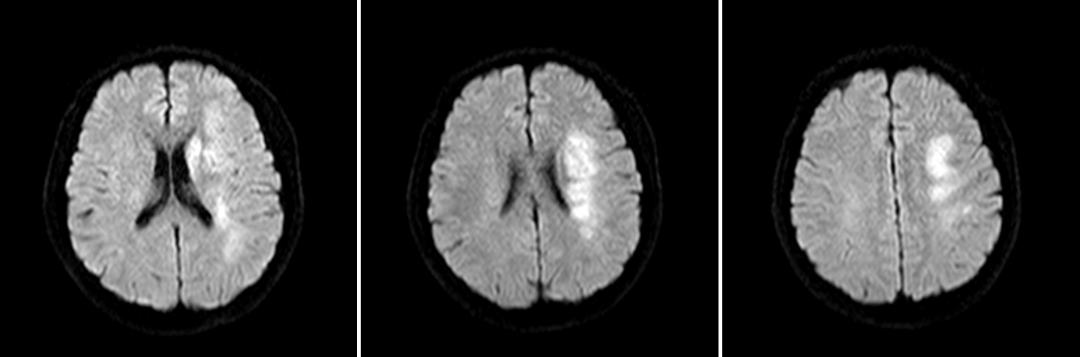

入院影像检查

DWI

重要影像结论:左基底节区及放射冠区脑梗死。